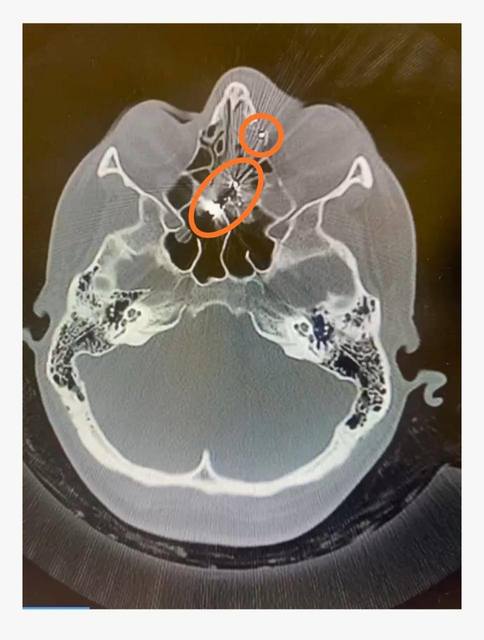

Бригада Петриківської підстанції прибули на виклик за лічені хвилини. Медики надали екстрену медичну допомогу за протоколом та транспортували постраждалу до Кам'янської лікарні швидкої медичної допомоги. Там під час комп'ютерного обстеження в неї виявили проникаюче кульове пневматичне поранення лівої очниці.